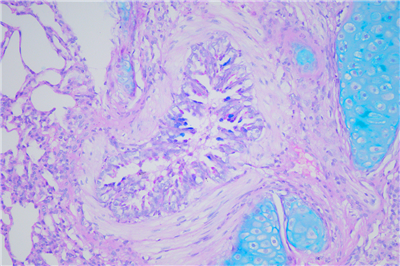

PAS染色步骤:

1脱蜡:65度30分钟,二甲苯脱蜡 5min×2次

2水化:将脱蜡后的切片经100%酒精,95%酒精,85%酒精,75%酒精,双蒸水各3min

3 入阿利新蓝染色液,染色15分钟。

4 蒸馏水洗3次,每次1-2分钟。

5 入过碘酸溶液,氧化5分钟

6入Schiff Reagent,浸染15分钟。

7 倾去Schiff Reagent,流水冲洗10分钟。

8(可选)入Leagene苏木素染色液,染核1-2分钟。

9用酸性分化液分化2-5秒,水洗。

10用Scott蓝化液反蓝,水洗3分钟。

11 逐级常规乙醇脱水。二甲苯透明,中性树胶封固。

12通过显微镜拍照,采集分析样本相关部位。